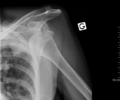

- An anterior dislocation of the shoulder

Anterior dislocation of the right shoulder. Y view X ray.